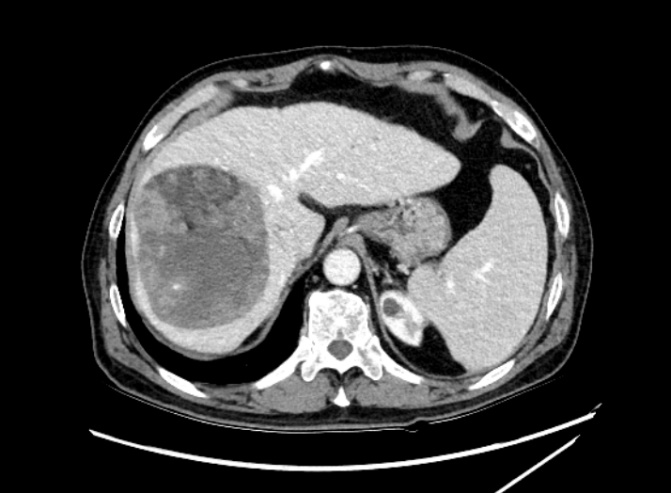

肿瘤体积超过半个肝 71岁的刘先生最近背部酸痛明显,活动受限,行走困难,就连晚上睡觉也只能趴着睡,但凡一扯到背部的肌肉,那种剧烈的疼痛让他直冒冷汗,连续贴了一个多月的膏药也无法有效缓解。 放心不下的他来到了浙江省人民医院越城院区就诊,医生为他做了胸片CT平扫后,发现他的肝脏部位隐隐约约有一个很大的肿块,建议做进一步的检查。 突如其来的噩耗让刘先生担忧不已,多方打听下,他慕名来到了肝胆胰外科、微创外科主任助理尚敏杰副主任医师处寻求帮助。 “经过磁共振等一系列检查,我们发现患者的右肝有个直径13公分的巨大恶性肿瘤,以及左肝也有一个鸡蛋大小肿块,两处肿瘤加起来,体积竟超过半个肝脏,甚至还有部分肿瘤已经累及横隔膜的可能。此外患者本身还有肝硬化、乙肝等疾病,治疗难度极大。” 术前左右肝可见占位 尚敏杰介绍,目前手术治疗是肝脏恶性肿瘤获得长期生存最重要的手段。好在患者肿瘤包膜完整,手术切除有价值,患者如果想要获得根治性切除,必须切除整个右侧半肝、左肝部分,以及部分膈肌,而根据三维成像技术电脑测算,切除所有肿瘤后,左侧半肝扣除左肝肿块后剩余肝体积不足45%,且患者有伴有慢性乙型肝炎肝硬化,属于极量肝切除。 术前拟保留肝脏体积标记计算 充分考虑后,刘先生最终还是选择了手术治疗。为了确保手术万无一失,肝胆胰外科、微创外科主任张成武主任医师与尚敏杰团队反复讨论手术方案、精心准备,最终在呼吸科、麻醉科、心血管内科等多个科室的大力配合下,手术顺利完成,肿瘤被完整切除,而且术中仅出血800毫升。术后患者出现一过性黄疸升高,进行了护肝治疗,并及时引流了在右胸腔内的反应性胸水,不久后患者整体体征逐渐趋于平稳,平安出院了。 术后复查残余部分左肝 3D成像软件精准评估 可耐受极量肝切除体积 肝脏可以切掉一部分吗? 肝脏是一个非常重要的器官,是人体代谢的中心,主要功能是分泌胆汁,参与蛋白质、脂肪、糖类的代谢,另外还有着解毒、凝血和造血的功能。一般情况下,正常的肝脏可以切掉一部分,只要残余体积不小于30%,肝细胞就可以代偿正常人体所需要的各种功能。 张成武介绍,肝脏切除后,剩余的肝脏会肥大再生,恢复到原来的体积,以适应机体的各种功能。 但是…… 如果患者本身肝脏有慢性肝炎、肝硬化等基础疾病,可能会导致肝脏的再生能力会减弱,恢复时间较久,一般手术后残余肝脏体积不能小于40%,如果切除体积超过此界限后,患者可能会出现肝脏功能不全甚至肝功能衰竭的风险,死亡率较高。 “一般来说,手术前我们往往都会评估患者肝脏的储备功能,通过CT图片用3D成像软件标记剩余的肝脏,计算剩余肝脏与标准肝体积的比值,来评估肝脏是否耐受极量肝切除体积。” 患者在肝脏切除手术后,肝脏合成蛋白的能力降低,因此补充优质蛋白非常必要,建议少量多餐,多吃含有优质蛋白的食物如鱼、虾、蛋、奶、瘦肉等。另外可以多吃些新鲜的蔬菜和水果,及时补充维生素,增强身体免疫力。避免过度劳累、熬夜。 肝胆胰外科、微创外科 浙江省人民医院肝胆胰外科、微创外科是浙江省医学重点学科(支撑学科)、浙江省重点学科群(微创外科学科群)核心科室,医院重中之重学科。以肝胆胰疾病微创手术治疗为特色,80%以上为微创手术,年均腹腔镜肝胆胰肿瘤手术超过500例,开展腹腔镜肝门部胆管癌根治性切除、腹腔镜胆囊癌根治术、腹腔镜巨大肝癌切除、腹腔镜二步肝切除、腹腔镜保留十二指肠的全胰切除、腹腔镜RAMPS手术等高精尖手术。另外,科室开展的腔镜减重和腔镜胃食管反流病等特色手术量居省内前三,综合实力居国内领先水平。